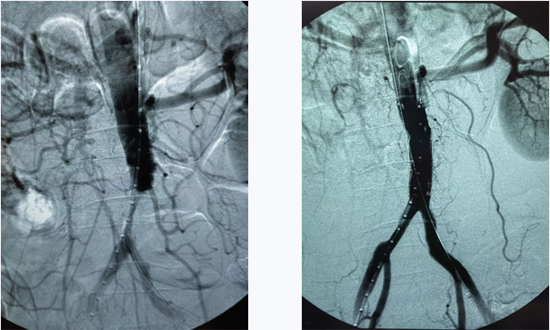

幸运的是在导管取出大量带分叉的血栓后,造影显示,虽然主动脉下段几近闭塞,但有了纤细的血流,给术者提供了输送修复支架的通道,显然外伤的腹主动脉还没有出现爆炸式破裂,给我们修复破口预留了时间和机会。于是,手术团队迅速置入一枚覆膜支架,对损伤的腹主动脉、双髂动脉进行重塑成型,球囊扩张后,造影显示闭塞的动脉恢复了通畅。至此病人已无术中突发猝死的危险。

然而,手术到此远没有结束。由于长时间缺少血流双下肢大动脉都已长满血栓,仔细将所有血管内的血栓清除才能保住肢体的血流,尽管已经过了黄金取栓期,手术团队还是想尽办法去除了所有血栓。整场手术历时3个多小时,结束时已经早晨七点了。术后病人双下肢皮肤颜色由苍白、花斑转为红润。